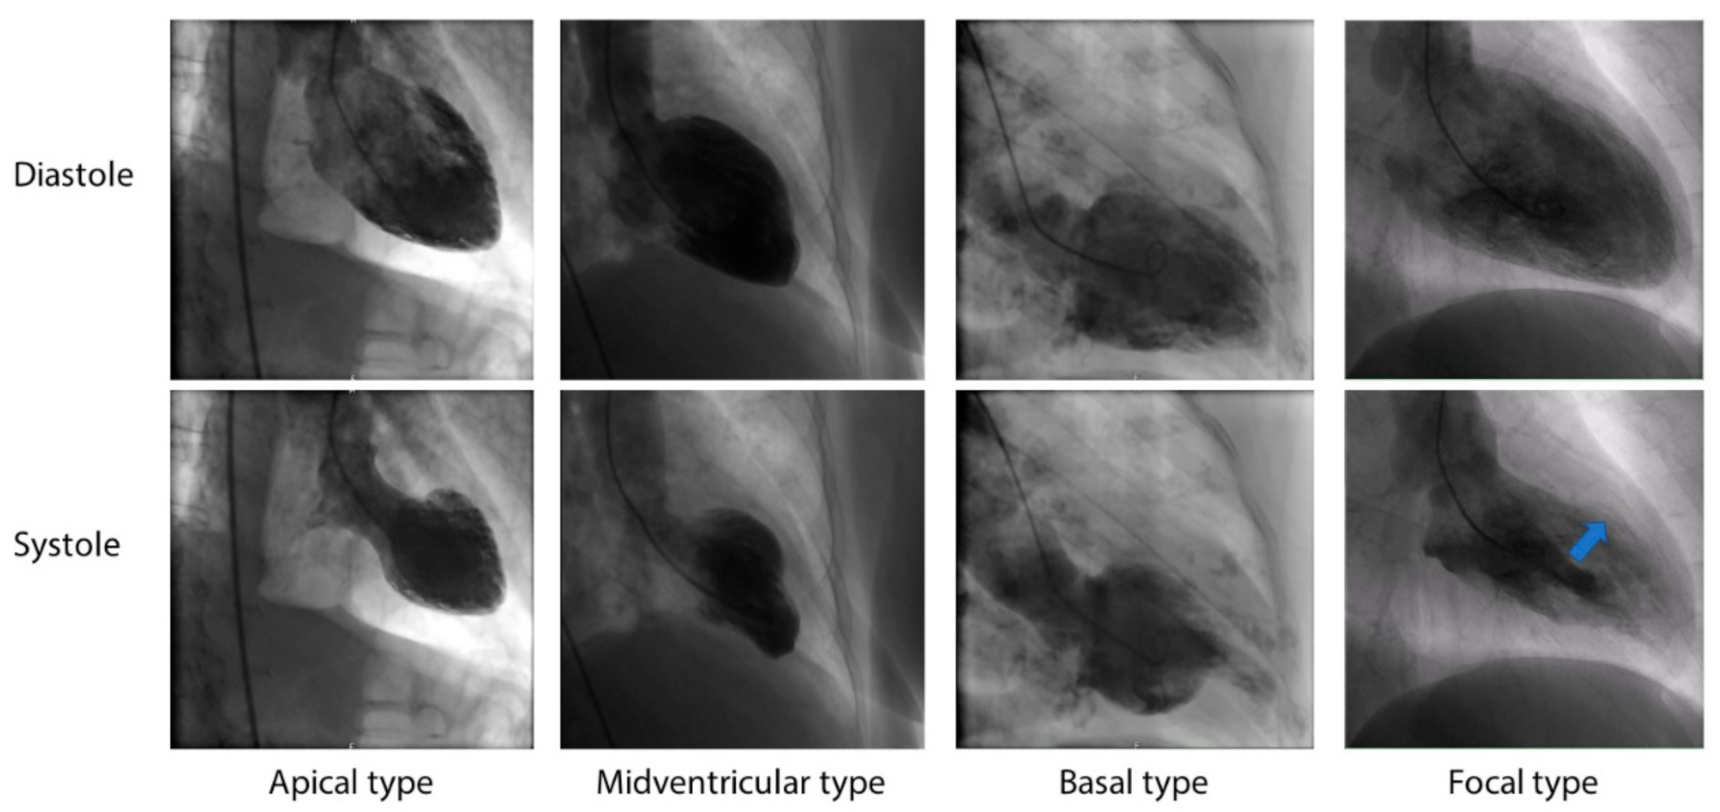

4.3. Angiography and Ventriculography

| Angiography and ventriculography | Absence of culprit atherosclerotic coronary artery disease including acute plaque rupture, thrombus formation, and coronary dissection, as well as characteristic regional LV wall motion abnormality (RWMA). Apical nipple sign. |